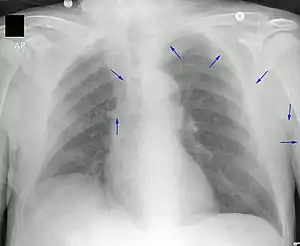

Un PICC est inséré dans une veine périphérique (en) telle que la veine céphalique, la veine basilique ou la veine brachiale du bras, puis il est enfilé dans les veines en direction du cœur, jusqu'à ce que l'extrémité du cathéter repose dans la veine cave supérieure distale ou la jonction cavoatriale (en). Ils doivent être insérés par un professionnel médical formé, notamment un médecin, mais aussi tout professionnel médical spécialement formé tel qu'une infirmière auxiliaire[6]. Une échographie médicale, une radiographie pulmonaire, ou encore l'utilisation de la fluoroscopie, peuvent être utilisées pendant l'insertion et pour confirmer le placement. L'insertion est une procédure stérile, mais il n'est pas nécessaire de la réaliser dans un environnement complètement stérile comme une salle d'opération.